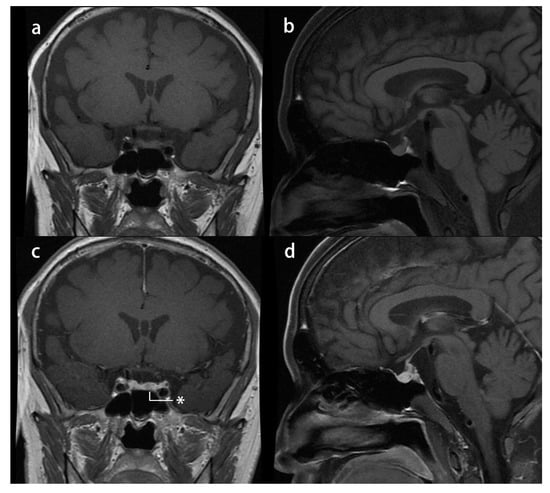

Case 2: A 29-year-old man with a 3-year history of hypertension and a 1-year history of central obesity, decreased libido, asthenia, and ostealgia was referred to our department. He had a history of renal calculus, rib fractures, and lumbar compressional fractures. An overnight 1 mg dexamethasone suppression test in another center could not suppress serum cortisol (16.6 µg/dL), and then he was referred to our center. His physical examination revealed moon face, central obesity, abdominal striae, and lower extremity edema. His height was 163 cm, and his weight was 61 kg, with a BMI of 22.96 kg/m2. His blood pressure was 170/125 mmHg. His midnight serum cortisol (21.25 µg/dL) and morning serum cortisol (19.7 µg/dL) showed impaired cortisol rhythmicity, and his ACTH was 37.5 pg/mL. Furthermore, his 24 h UFC was 185.8 µg. A low-dose dexamethasone suppression test could not suppress 24 h UFC (43.7 µg), whereas a high-dose dexamethasone suppression test suppressed 24 h UFC (20.8 µg). Dynamic pituitary MRI suspected a 3 × 4 mm hypointense nodule at the left side of the pituitary (Figure 3). To verify this finding, bilateral inferior petrosal sinus blood was sampled under a desmopressin acetate activation test. It confirmed an asymmetrical secretion of ACTH in the left part of the sellar region, as the central (left)/peripheral plasma corticotropin gradient without activation was 3.9 (66.8/17.2 pg/mL), and this gradient exceeded 55 (>1250/22.6 pg/mL) after 3 min of desmopressin activation. Hence, CD was suspected. The patient underwent endoscopic transsphenoidal surgery. A white-gray, soft, and poorly vascular lesion was noticed, and a gross total section was achieved. After surgery, the remission of hypercortisolism was achieved, with no relapse in 8 months of follow-up. The patient developed hypopituitarism, and hence, he was discharged with a prescription of 20 mg hydrocortisone acetate daily (in three divided doses), 25 µg levothyroxine daily, and 0.25 g testosterone undecanoate injection once a month.

Figure 3.

Presurgical pituitary MRI study of case 2: (a) T1-weighted image (T1-WI) coronal plane and (b) T1-WI sagittal plane showing a normal pituitary stalk without any nodule; (c) T1-WI contrast-enhanced coronal plane reveals a hypointense nodule* in the left side of the pituitary gland; and (d) T1-WI contrast-enhanced sagittal plane.